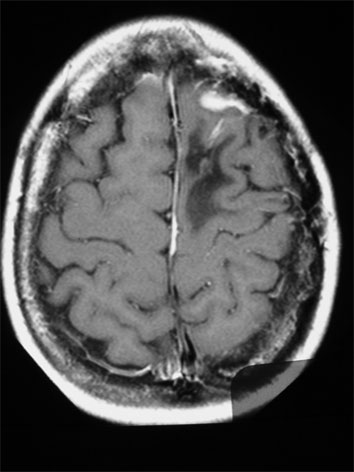

Tratamiento de Meningioma con Radiocirugía Estereotáxica. Paciente había sido operada a craéneo abierto en dos ocasiones, y viene por recurrencia del tumor

Resonancia magnética al momento de la radiocirugía